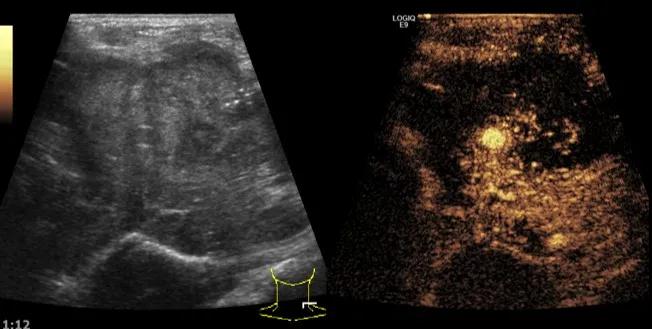

随后,徐栋教授进一步分享了五个临床实战病例,带来了更直观的热消融治疗经验。第一个病例是62岁肺癌患者,术后1年余发现双侧锁骨上淋巴结复发,侵犯神经,存在静脉回流、淋巴回流障碍,肿胀、疼痛非常明显。影像显示患者淋巴结边界不清、形态不规则,存在浸润,血流强化增强。由于患者在系统治疗后进展,且主要目的缓解症状、减瘤。局麻下行热消融术,从后向前逐层消融,热消融之后超声造影即刻评估显示完全充盈缺损,完全覆盖病灶。

(病例1图例)